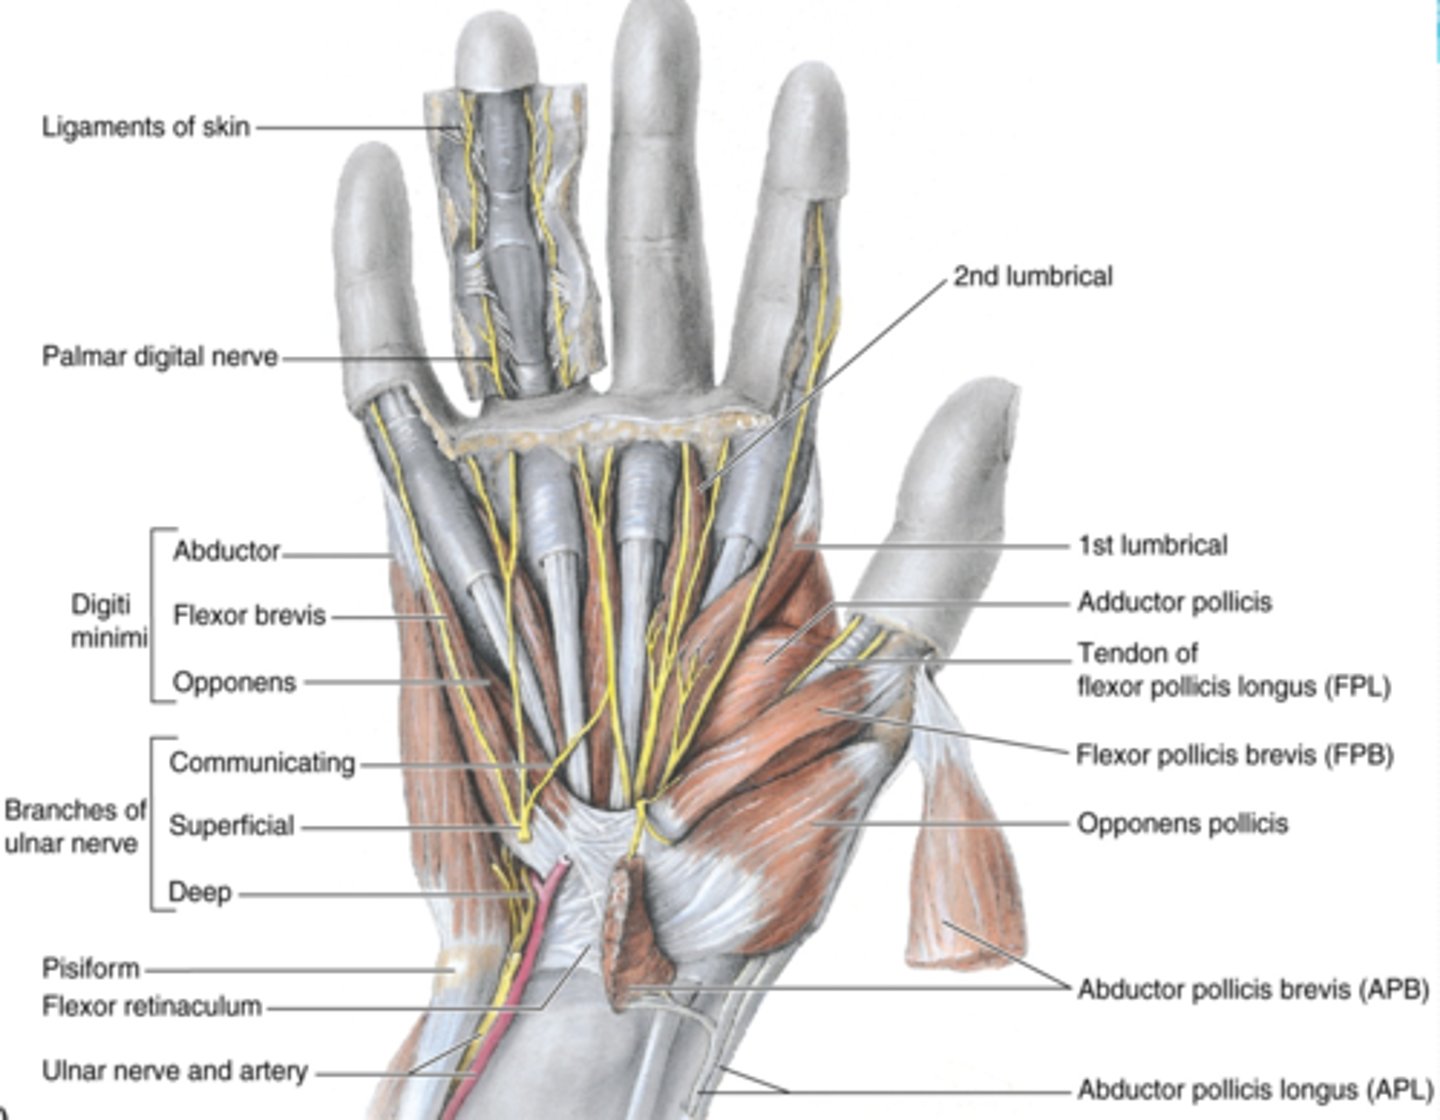

(Muscles of hand:) Muscles of thenar eminence

These muscles are responsible for opposition of thumb

-Abductor pollicis brevis (APB)

-Flexor pollicis brevis (FPB)

-Opponens pollicis

-Abductor digiti minimi

-Flexor digiti minimi

-Opponens digiti minimi

(Muscles of thenar eminence:) Abductor pollicis brevis (APB)

-Abducts 1st digit (thumb), helps opposition

-Median n. (C5 - T1)

-Forms anterolateral part of thenar eminence

(Muscles of thenar eminence:) Flexor pollicis brevis (FPB)

-Flexes 1st digit (thumb)

-Median n. (C5 - T1)

-Medial to APB

(Muscles of thenar eminence:) Opponens pollicis

-Opposes 1st digit (thumb)

-Median n. (C5 - T1)

-Deep to APB

(Muscles of thenar eminence:) Abductor digiti minimi

-Abducts 5th digit

-Ulnar n. (C7 - T1)

-Most superficial of the hypothenar muscles

(Muscles of thenar eminence:) Flexor digiti minimi

-Flexes 5th digit

-Ulnar n. (C7 - T1)

-Lateral to abductor digiti minimi

(Muscles of thenar eminence:) Opponens digiti minimi

-Rotates 5th digit bringing it into opposition with the thumb

-Ulnar n. (C7 - T1)

-Deep to abductor and flexor digiti minimi muscles

Short muscles of hand

lumbricals, dorsal interossei (4) , palmar interossei (3)

(Short muscles of hand:) Lumbricals

-Flex fingers at metacarpophalangeal joints and extend interphalangeal joints of 2nd - 5th digits

-Median n. (C5 - T1)

(Short muscles of hand:) Dorsal interossei (4)

-Abduct fingers

-Ulnar n. (C7 - T1)

-Between the metacarpal bones

(Short muscles of hand:) Palmar interossei (3)

-Adduct fingers

-Ulnar n. (C7 - T1)

-On the palmar surface of metacarpal